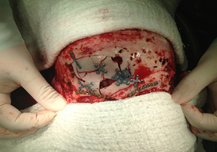

II. CIRUGIA PARA ENFERMEDADES CONGENITAS Y SINDROMATICAS (CROUZON, APERT, AVANZAMIENTOS)

III. PROCEDIMIENTOS NEUROQUIRURGICOS ONCOLOGICOS .

IV. MICROCIRUGIA DE LA BASE DEL CRANEO, Y ENDOSCOPIA CEREBRAL